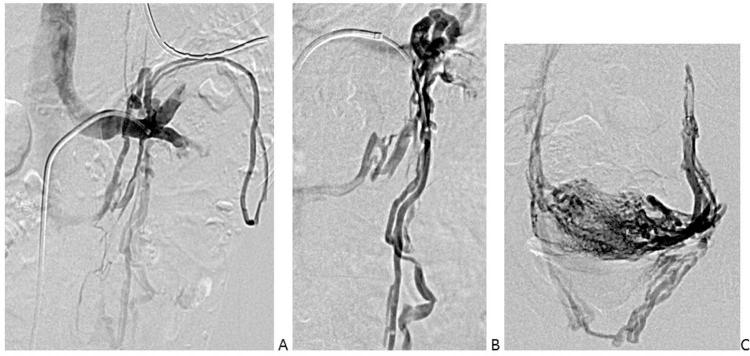

Nutcracker syndrome in adolescent with perineal pain: An interesting case of an adolescent with perineal pain due to pelvic congestion from nutcracker syndrome with relief after balloon venoplasty and sclerotherapy.

Nutcracker phenomenon is the descriptor for a patient's anatomy whenever the left renal vein becomes compressed between the abdominal aorta and the superior mesenteric artery. Nutcracker syndrome is the terminology used when the nutcracker phenomenon is accompanied by symptoms including pain (abdominal, flank, pelvic), hematuria, and orthostatic proteinuria. Diagnosis can be made with Doppler ultrasound, venography, computed tomography, or magnetic resonance imaging. This case demonstrates some of the typical findings of nutcracker syndrome. The limited clinical features and interesting imaging findings, in addition to the young age of the patient, make this a notable case.